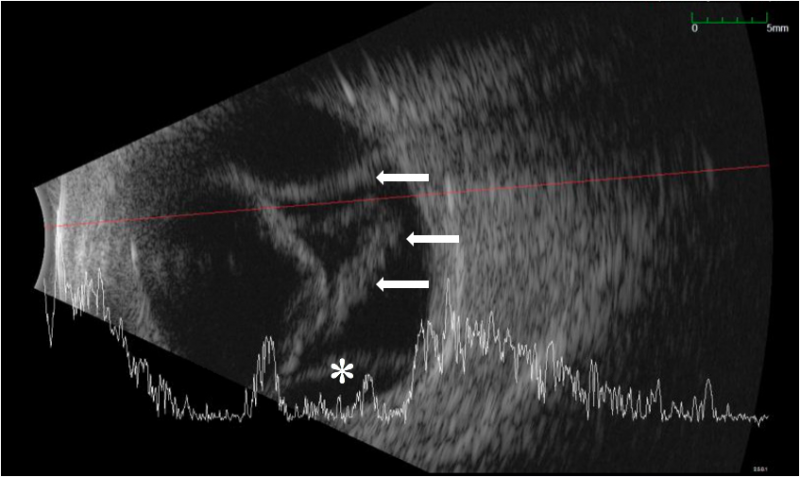

Figure 2: B-scan ultrasound demonstrating a total retinal detachment (white arrows) with concomitant choroidal detachment (white asterisk) in a patient with iris retraction syndrome.